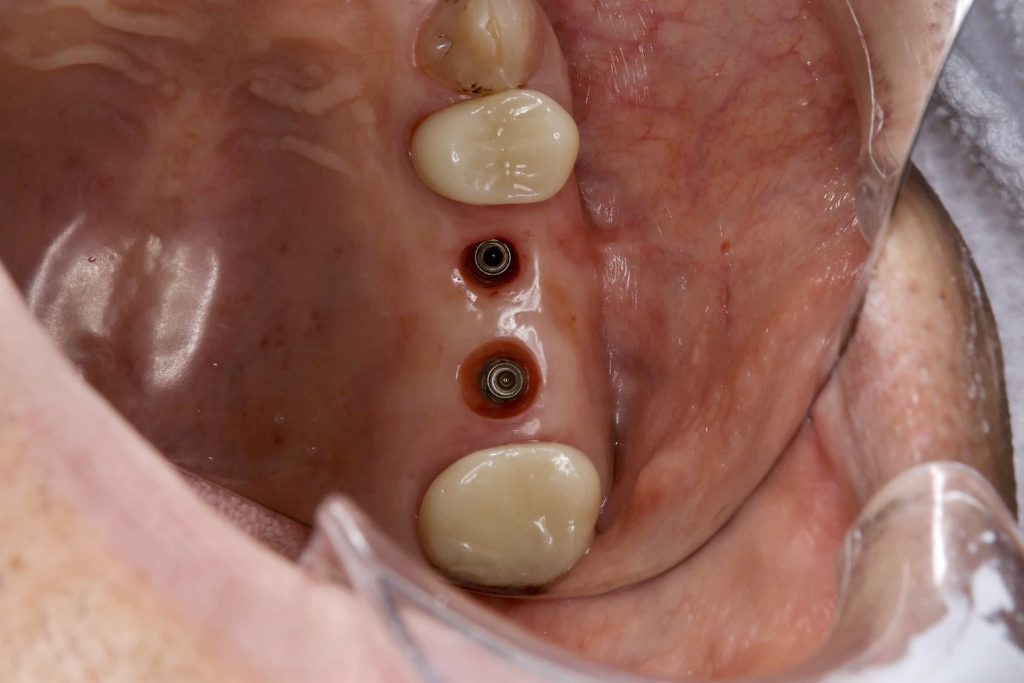

50代、男性、左上に違和感があることを主訴に来院され、インプラント治療を行いました。

| 治療内容 | 抜歯即時インプラント |

| 治療期間 | 10週間 |